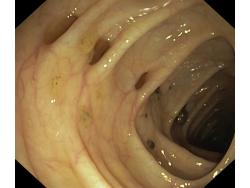

Uchyłki